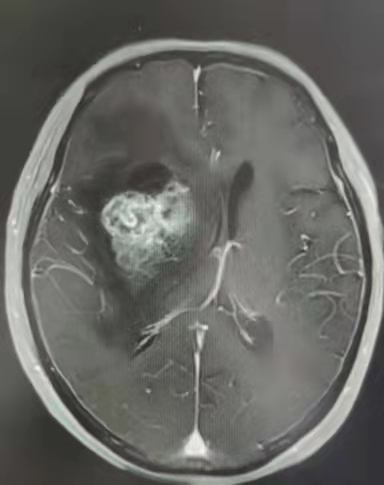

术后复查可见肿瘤基本切除

术后黄爷爷功能恢复好